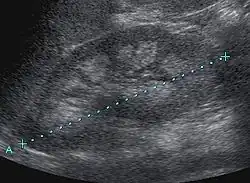

Nephrocalcinosis is diagnosed for the most part by imaging techniques. The imagings used are ultrasound (US), abdominal plain film and CT imaging.[10] Of the 3 techniques CT and US are the preferred modalities.

- Macroscopic nephrocalcinosis: Occurs when calcification can be seen through X-ray imaging.[1]